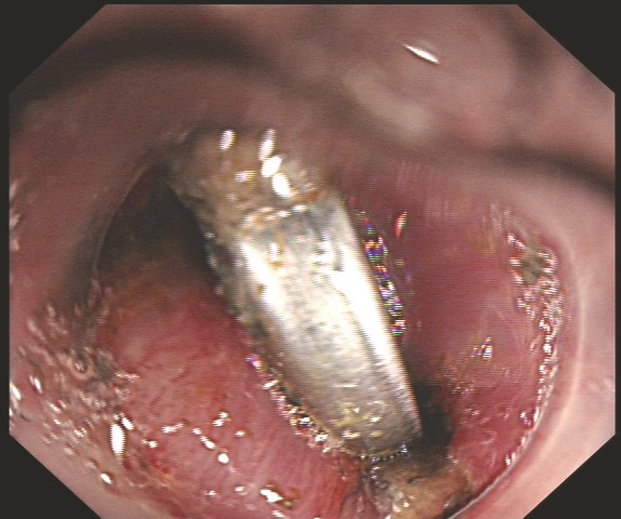

在内镜中心团队人员的精心操作下,细长的内镜轻柔探入,高清画面实时传回:那枚银色的纽扣电池,正紧紧嵌顿在食管入口第一狭窄处!孩子太小,纽扣电池大,电池死死地卡在食管入口处,操作空间有限,电池边缘太滑,种种的困难与挑战摆在医护人员面前,这是一场与时间的拉锯战。过程是艰辛的,但结果是好的,这枚危险的“定时炸弹”终于被完整取出,检查确认食管黏膜仅有轻微损伤,所有人悬着的心终于落地。